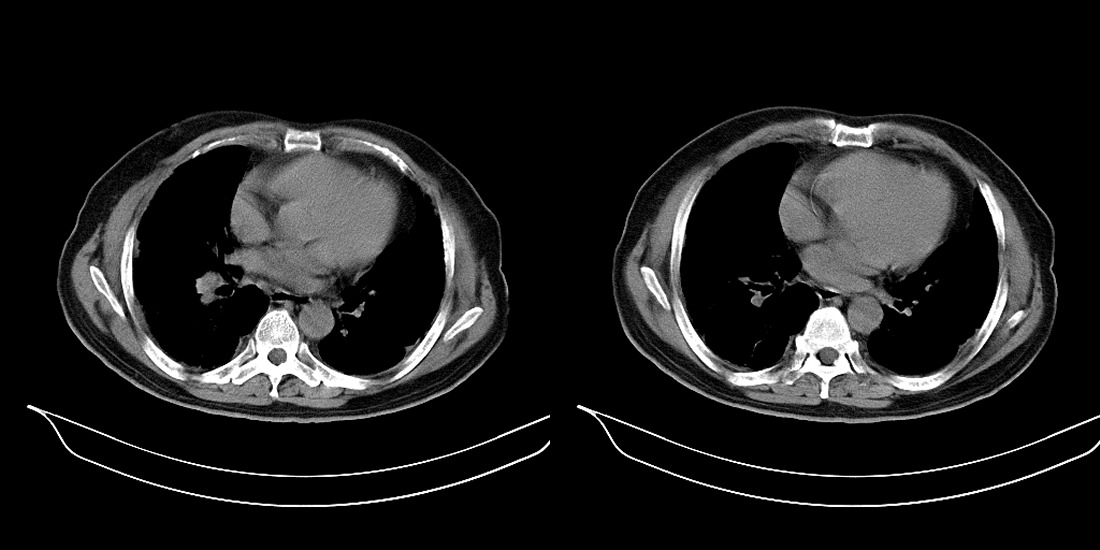

以下是引用zsl6918在2008-2-14 12:15:00的发言:[br]慢支并感染,肺气肿,肺间质纤维化,肺动脉高压。

以下是引用liuyue在2008-2-14 17:25:00的发言:[br]慢支并感染,肺气肿,肺间质纤维化,肺动脉高压 .肺大泡.[br]

以下是引用随光逐影在2008-2-15 11:10:00的发言:[br]1)慢性支气管炎并肺部感染。2)肺间质纤维化。3)肺气肿(多发性肺大泡形成)。4)肺动脉高压。